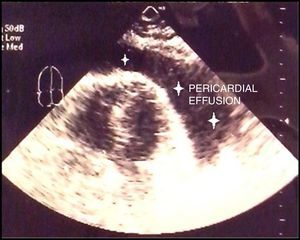

Two weeks after discontinuation of corticosteroid therapy, the patient presented with chest pain, tachypnea and dyspnea, and was found to have massive pericardial effusion (Fig. 2), requiring pericardiocentesis (1400cc of bloody fluid). Culture of the pericardial fluid was negative for common microorganisms and acid- and alcohol-fast bacilli. The pathological finding was nonspecific chronic pericardial sclerosis. Computed tomography of chest, abdomen and pelvis showed no evidence of tuberculosis or neoplasm. Treatment was begun with colchicine and prednisone at 40mg/d, and subsequently with azathioprine at 150mg/d, and the pericardial effusion completely resolved. The prednisone dose was tapered over 2 years. At no time during the aforementioned systemic processes did the patient show signs of active arthritis or radiographic evidence of notable joint destruction.